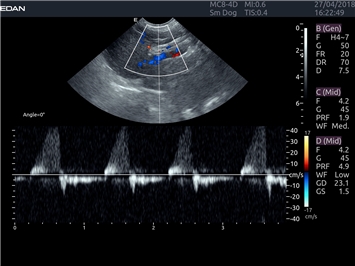

EDAN Acclarix LX4 VET представляет собой профессиональную ультразвуковую систему, специально разработанную для ветеринарных исследований. Сочетание стабильности, высокой производительности и эффективности делает эту систему идеальным выбором для современной ветеринарной практики.

Цветовой допплер:

Да

Импульсно-волновой допплер:

Постоянно-волновой допплер: